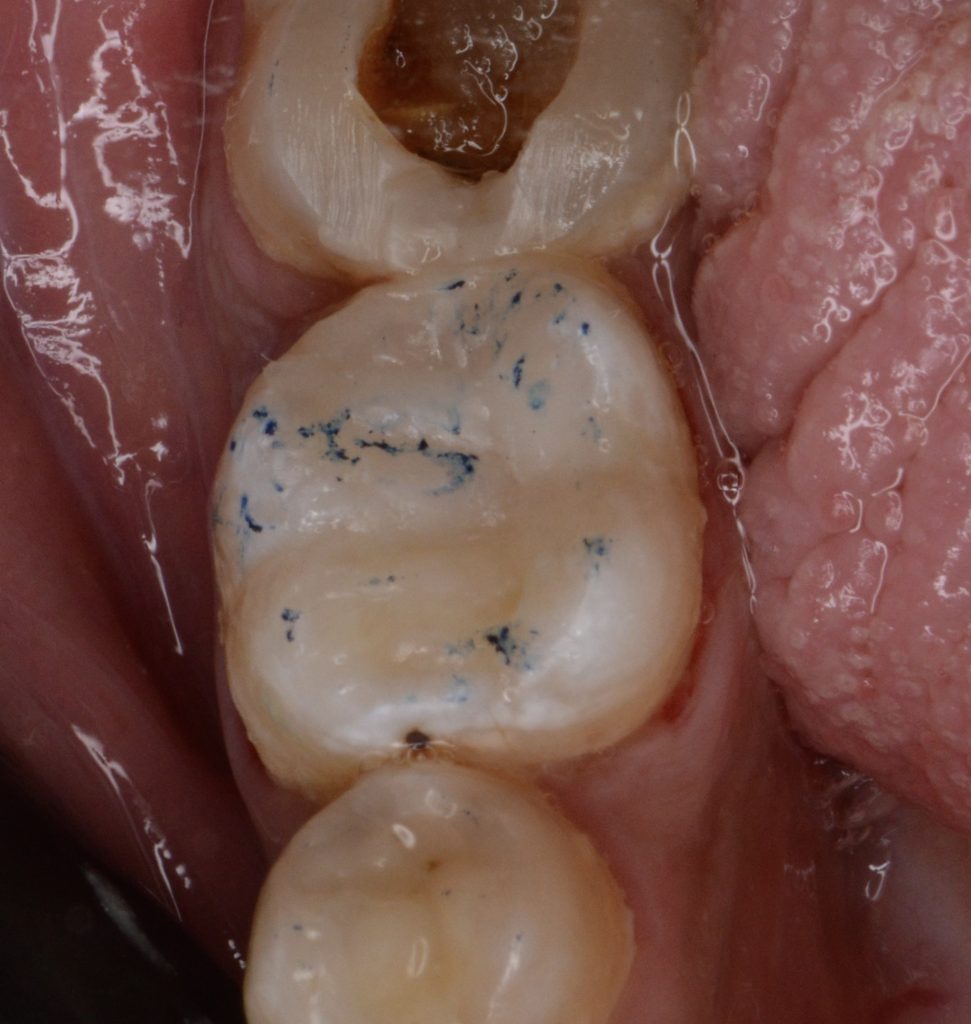

today we’re presenting a direct coronal seal approach using contemporary steps in order to be minimally invasive and keep as much as integral tooth structure as possible, God willing.

(Of course, indirect workflow will help in providing a closer structure to enamel, but the available plan was the direct one in a patient-tailored treatment).